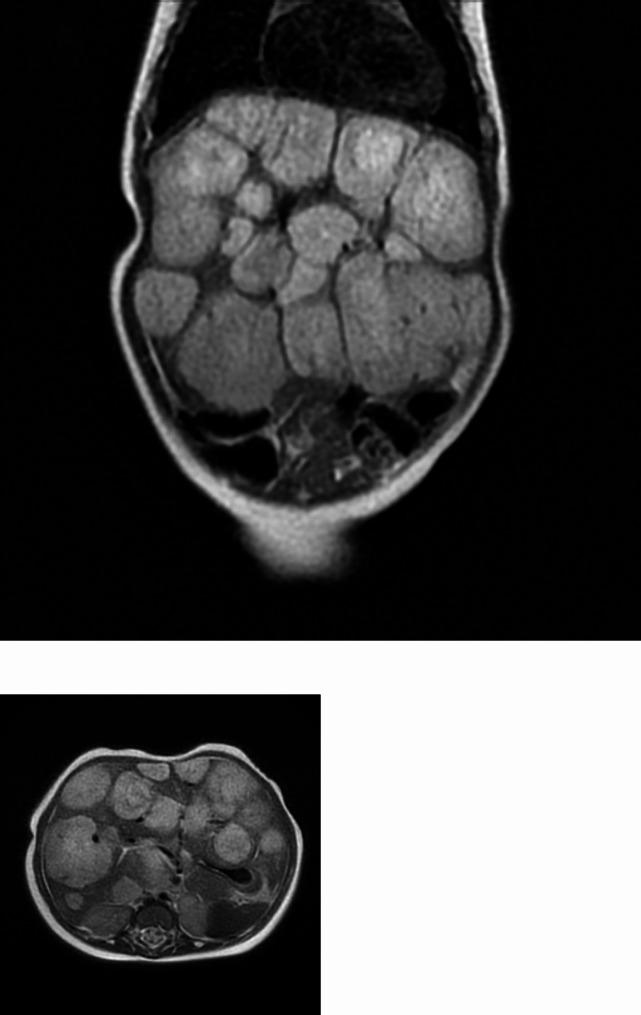

Case presentation: We report the case of a two-month-old female with the first diagnosis of late-onset congenital hypothyroidism, associated to unexplained anemia and significant increase of transaminases and gamma-GT. She promptly started treatment with levothyroxine (10 mcg/kg/day). To identify the etiology of hypothyroidism, anemia and increased liver enzymes, she underwent an abdominal ultrasound, that evidenced infantile diffuse hepatic hemangiomatosis, confirmed by abdominal MRI. Brain MRI showed a few millimetric areoles, compatible with microangiomas. The patient needed a significant increase of levothyroxine dosage, reaching a difficult normalization of TSH, fT4 and fT3. Ten days after the start of treatment with propranolol, a significant reduction in liver hemangiomatosis occurred, confirmed by the reduction of alpha-fetoprotein, AST, ALT, gamma -GT and TSH levels. The patient required a progressive reduction of levothyroxine dose, with the improvement of hematologic parameters. The child's auxological growth and neuromotor development occurred in an age-appropriate manner.